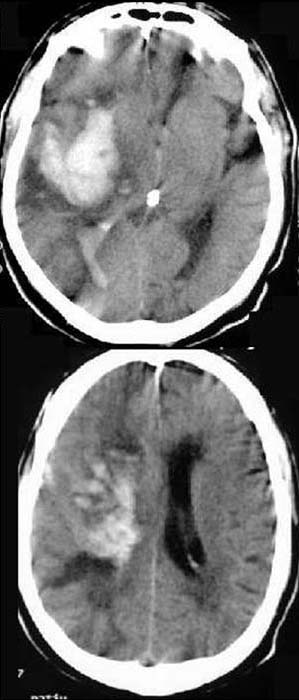

CCT nativ (ohne Kontrastmittel).

Hyperdense

(60-80HE) Raumforderung rechts im Bereich der Capsula interna und der

Basalganglien. Mittellinienverlagerung nach

links. Asymmetrische

Darstellung des Ventrikelsystems (rechts komprimiert, links gestaut).

Hyperdenser

Verhalt im rechten und linken Hinterhorn. Verstrichene

Gyri und Sulci rechts (siehe Seitenvergleich).

Hypertensive

Hirnmassenblutung rechts mit konsekutiver

raumfordernder Wirkung nach links

Kompression des rechten Ventrikels und Stauung des linken Ventrikels.

Einblutung ins Ventrikelsystem

Hirnödem